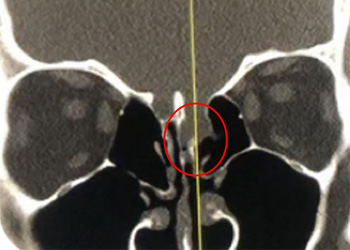

This is a 39-year-old, otherwise healthy woman who presented with right sided headaches for several months’ duration. MRI was performed and did not reveal a stroke […]

Collateral venous drainage into the orbit and skull base was observed (Fig. A). After successful cannulation of the direct aperture between the right carotid artery and […]